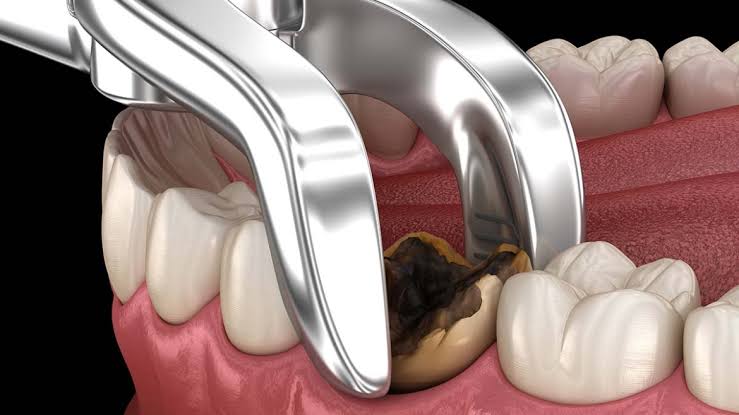

لما بنخلع السنه بيحصل bleeding in socket

و عليها طبقه من platelets

لحد ما الدم اللى ف socket يتجلط و

يكون blood clot

فى خلال15-20 minutes

أن اكسر كربوله بنج على قطنه

او احط foam gel

او كابرون أو هيموستوب